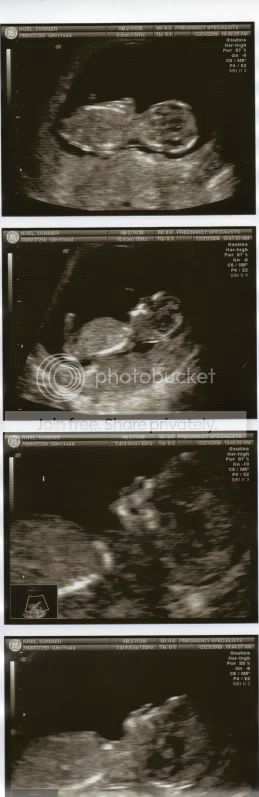

NT Scan- Update & PIP

I was so nervous that I gave myself an upset stomach & I was actually in the bathroom when they called my name. The NT Scan went great... By LMP is should be 11w4d and he is measuring at 12w4d. His HR was 168. He was the cutest thing I've seen in my entire life! When we first saw him he was standing upside down, then rubbing his nose, maybe sucking his thumb, wiggling all over the place. It was amazing and this is probably the best day in my life so far! He looks like a baby now, with his little profile and nose!